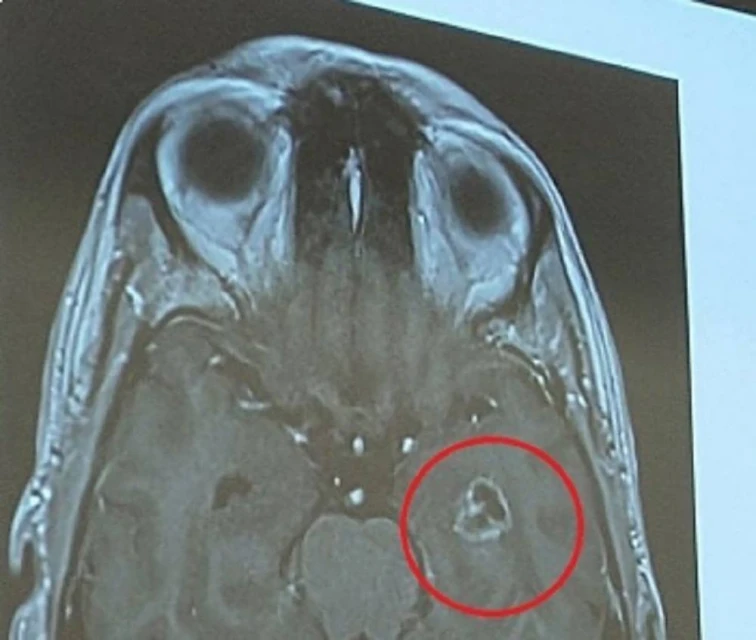

由於沙達雅的腫瘤正好長在腦部控制情緒的杏仁核(amygdala),其主治醫生、新加坡國大醫院神經外科主任兼高級顧問醫生姚進財臨床副教授說,沙達雅的憤怒,可能是因為腫瘤阻礙了大腦的這部分功能所致。」

患罕見腦癌性情大變 男子動手術救回一命 沙達雅的腫瘤剛好壓在腦部控制情緒的部位。

「膠質母細胞瘤可以長在大腦的任何地方,但這個案例就剛好長在杏仁核。」